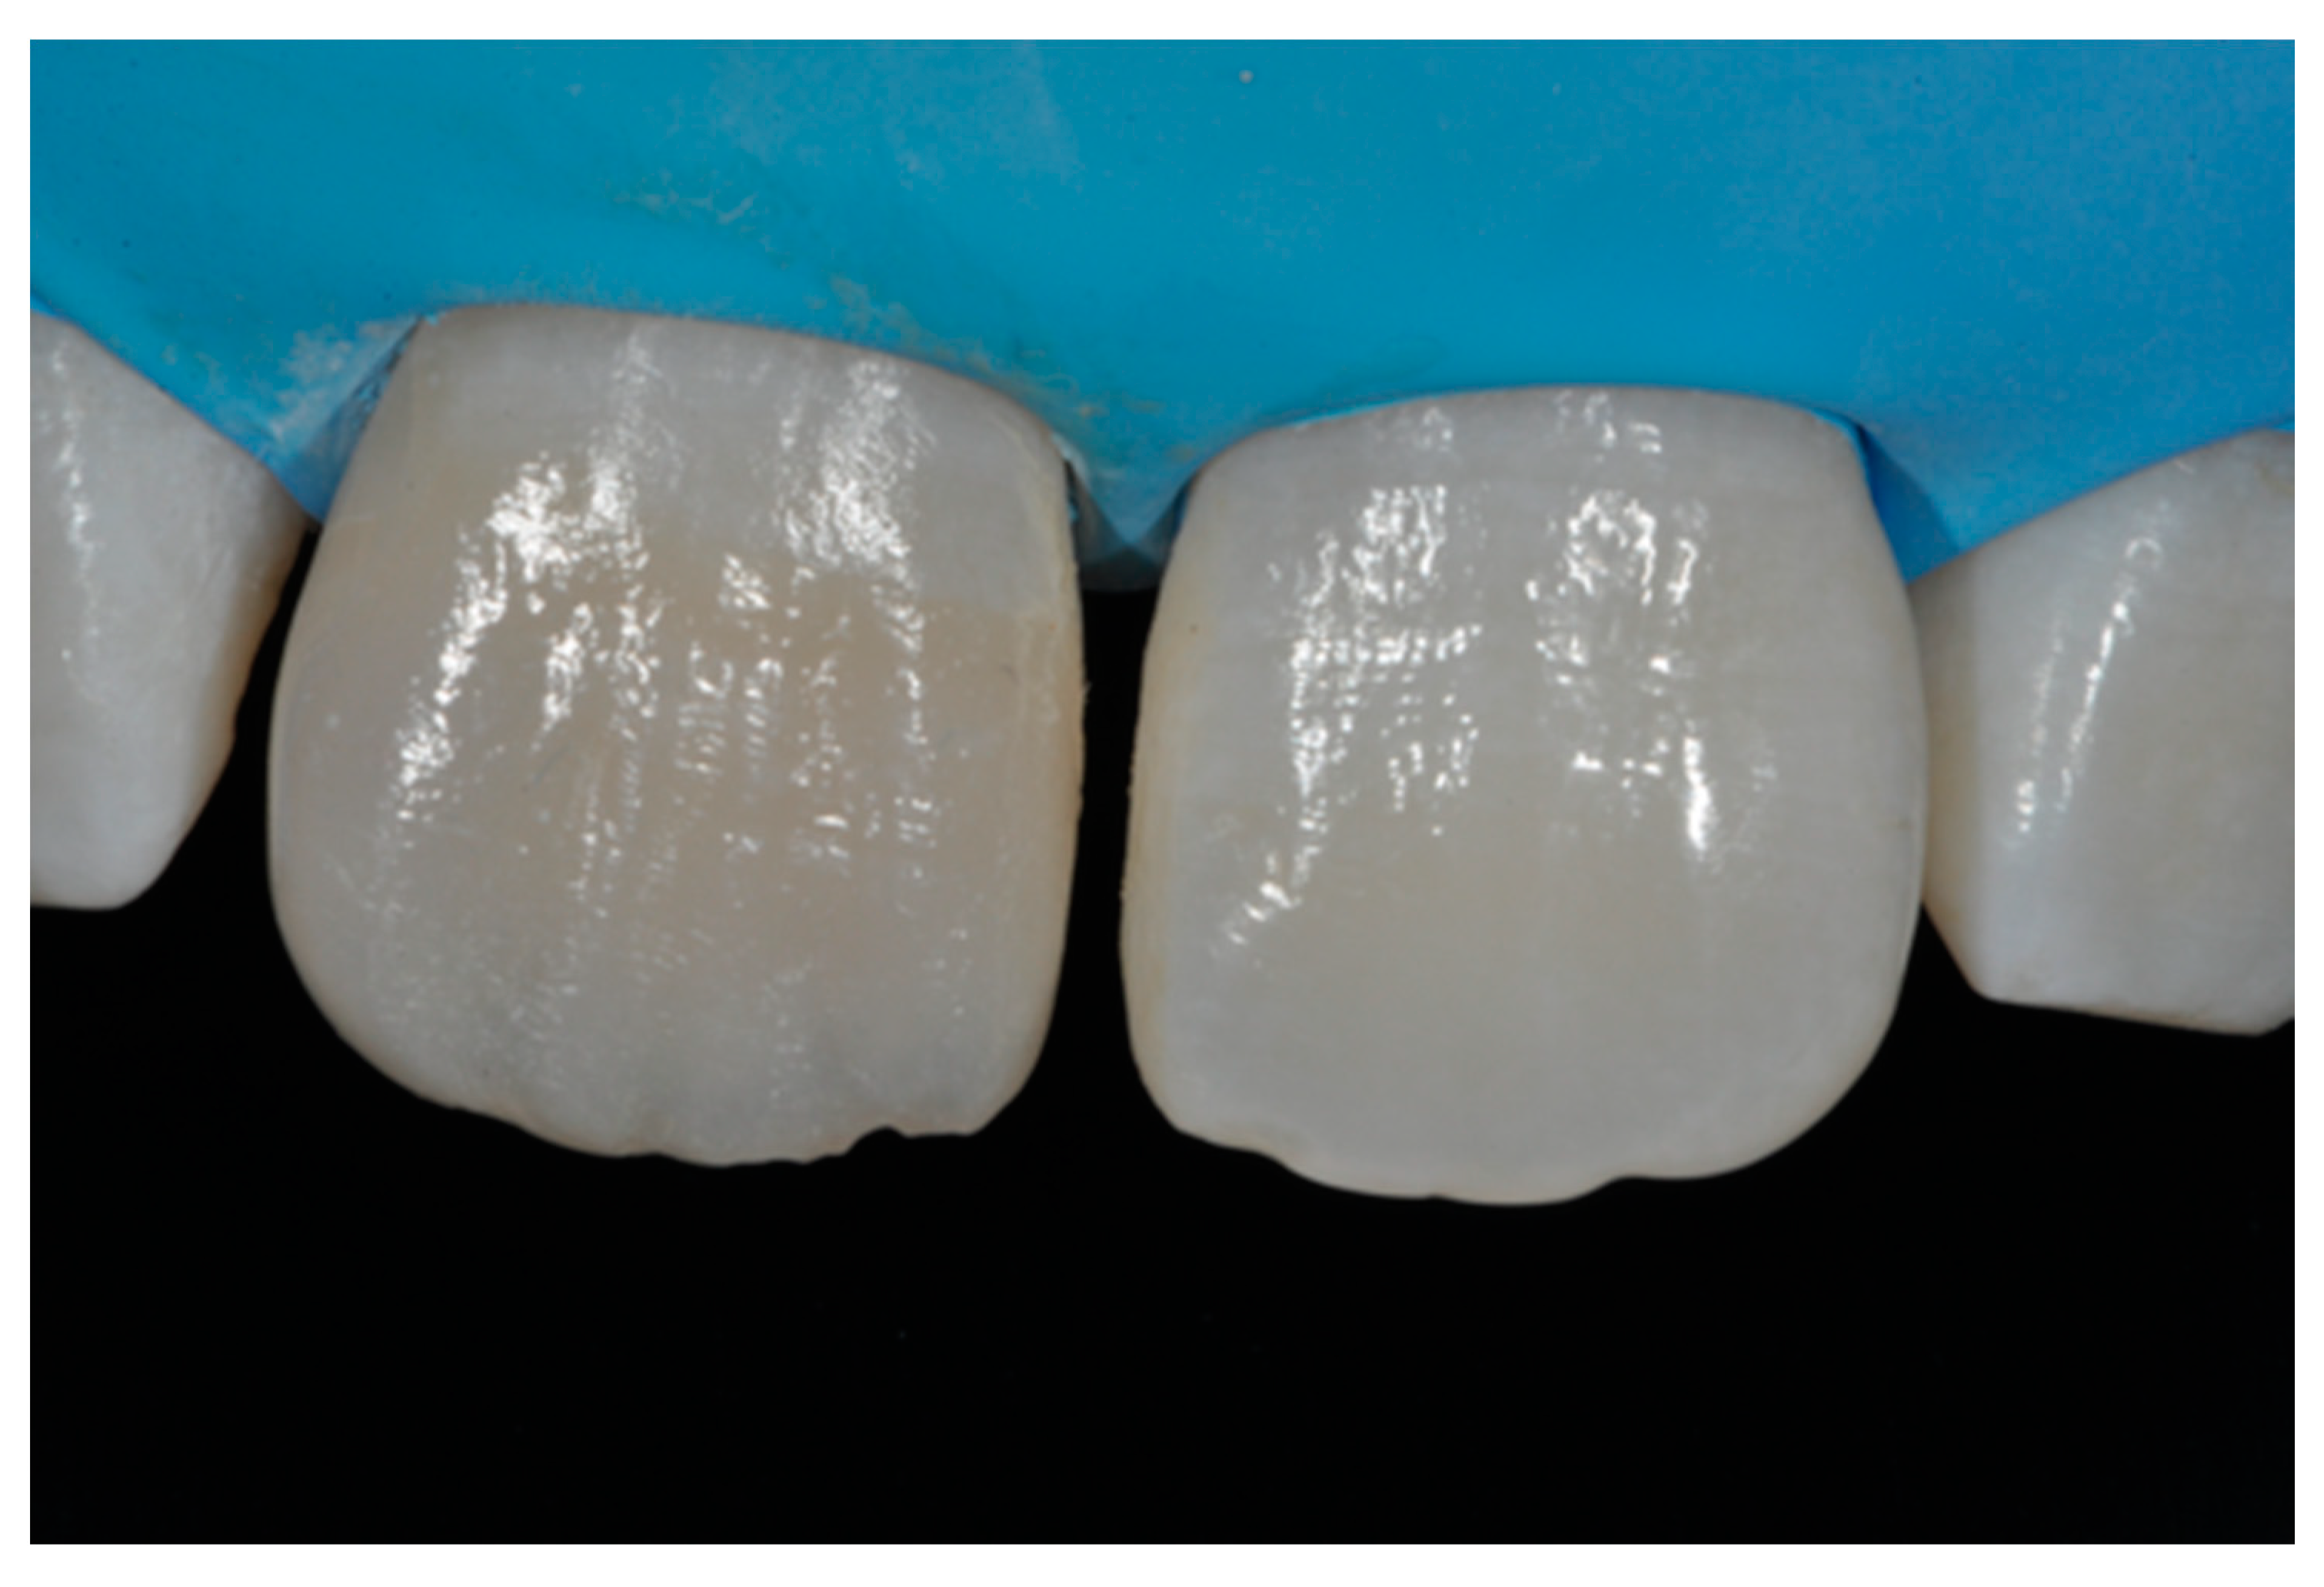

Figure 13.

Vertical and horizontal anatomy outlined with a pencil. Reprinted from Restauri diretti nei settori anteriori, G. Paolone, S. Scolavino, © 2021, with permission from Quintessence Publishing Italy.

Figure 14.

After vertical and horizontal anatomy definition and final polishing. Reprinted from Restauri diretti nei settori anteriori, G. Paolone, S. Scolavino, © 2021, with permission from Quintessence Publishing Italy.